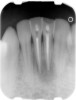

Case 1

A Class IN maxillary bicuspid was previously restored with a fiber post and an all-porcelain crown (Figure 1). The forces of the oral environment resulted in fracture of the fiber post and crown failure. The remaining fiber post in the root was removed, and anti-rotational areas were prepared for a cast post (Figure 2). A gold cast post was constructed at a dental laboratory, using an indirect technique (Figure 3). A porcelain-fused-to-metal (PFM) crown was constructed with a bevel finish to provide a ferrule and reduce forces on the post (Figure 4 and Figure 5).

Figure 2  Same second bicuspid as Figure 1 after removal of the fractured fiber post.

Figure 2